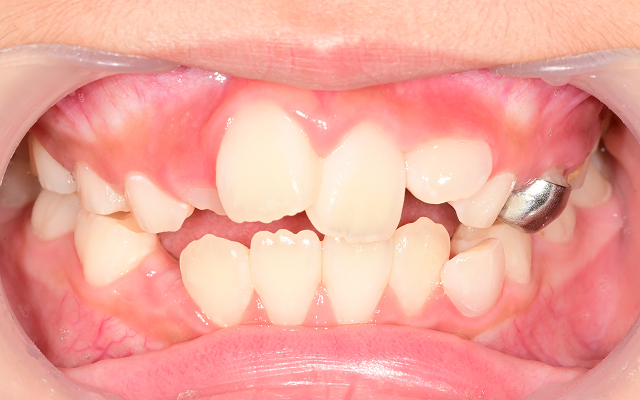

전통적인 장치 교정

턱 성장 방향을 조절하거나, 유치공간을 확보하는 장치를 사용합니다. (가철식 장치, 확장 장치, 헤드기어 등)